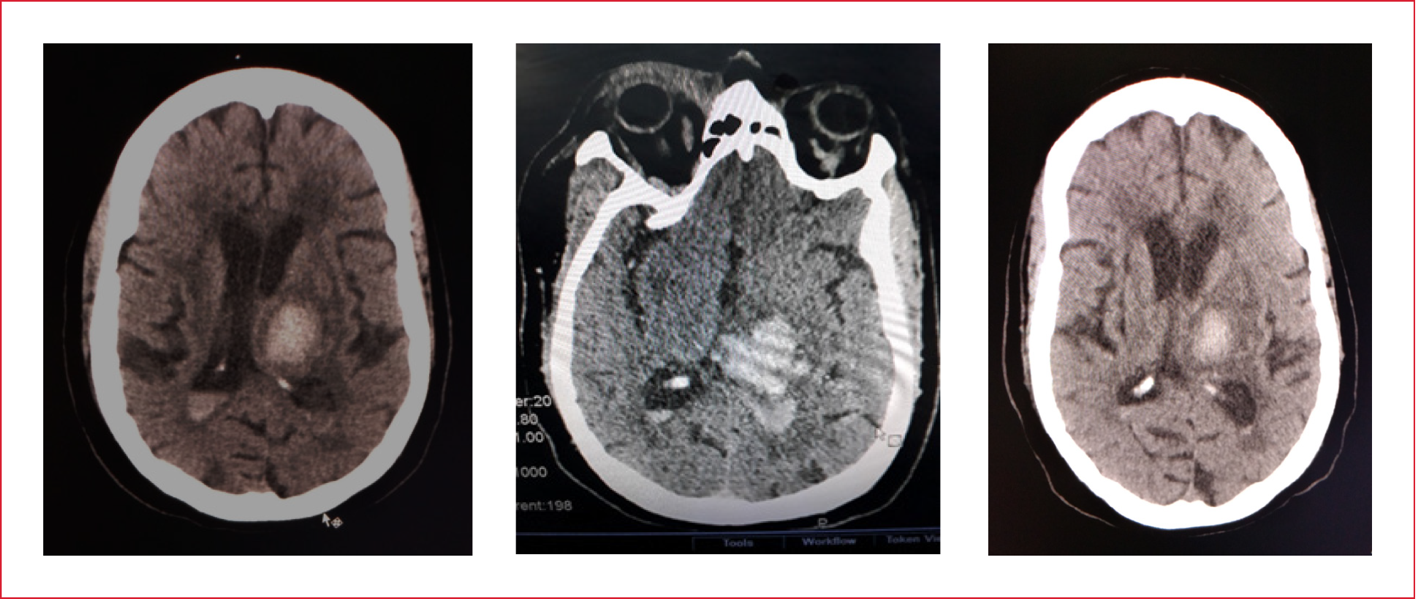

Presentación de caso: paciente de 58 años, femenina, historia de HTA y DM tipo 2 admitida en el hospital Victoria de Seychelles por emergencia hipertensiva e ictus diagnosticandosele por TAC hemorragia intracerebral talamica izquierda con sangrado intraventricular y edema cerebral ademas de neumonia por broncoaspiracion requiriendo soporte ventilatorio. Presento complicaciones: distress respiratorio, barotrauma, neumonia asociada a la ventilación mecánica, bacteremia asociada a catéter venoso central, y enfermedad tromboembolica: trombosis venosa profunda femoral derecha y tromboembolismo pulmonar. A pesar de su evolucion torpida es egresada viva.

Conclusiones: se diagnosticó de Hemorragia Intracerebral complicada egresada viva de los cuidados intensivos.